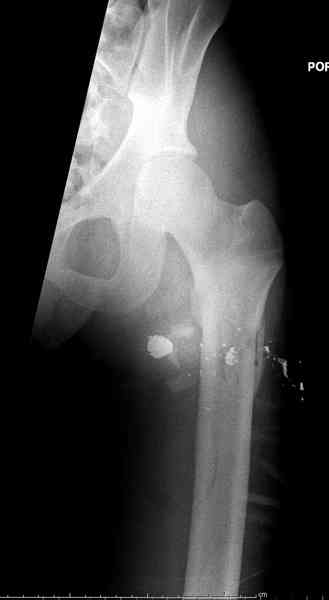

В нашем случае 21 летний боец уличного фронта, фиксацию провели на следующий день, зафиксирован интрамедуллярным штифтом. Не стали делать первичную хирургическую обработку точечной раны, зафиксирован как есть. Клинические снимки:

Конечно, наш случай не эталон, возможно, на месте вам виднее, может быть, нет необходимости ориентироваться на зарубежные ссылки, если получается лечить аппаратом Илизарова на месте, почему нет? Необходимо посмотреть собственный арсенал, чем фиксировать, и какая теория, иначе любой отличный метод можно превратить в источник остеомиелита.